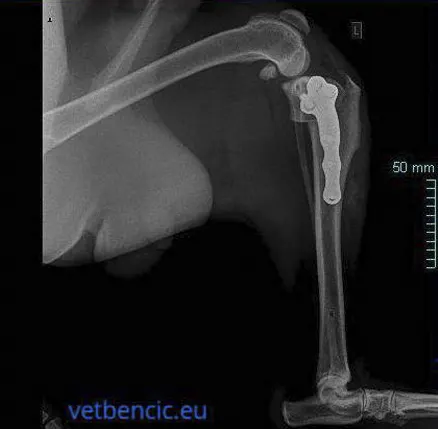

Vrlo složeni operativni zahvat koji uključuje odsijecanje cijelog bolesnog zgloba. Glava bedrene kosti se zamjenjuje metalnim implantatom, a zglobna čašica plastičnim ili metalnim implantatom. Implantati su pričvršćeni za kost uz pomoć koštanog implantata ili imaju spužvastu ovojnicu kroz koju kost može prodrijeti. Umjetni kuk se najčešće ugrađuje velikim psima, ali se može ugraditi i malim psima i mačkama. Kod pacijenata kod kojih je potrebna intervencija na oba kuka, intervencije se nikad ne rade istodobno zbog većeg rizika od komplikacija. Uspješnost ove intervencije je 90-95%, a nakon nekoliko dana pacijenti normalno hodaju. Većini pasa vraća punu aktivnost.